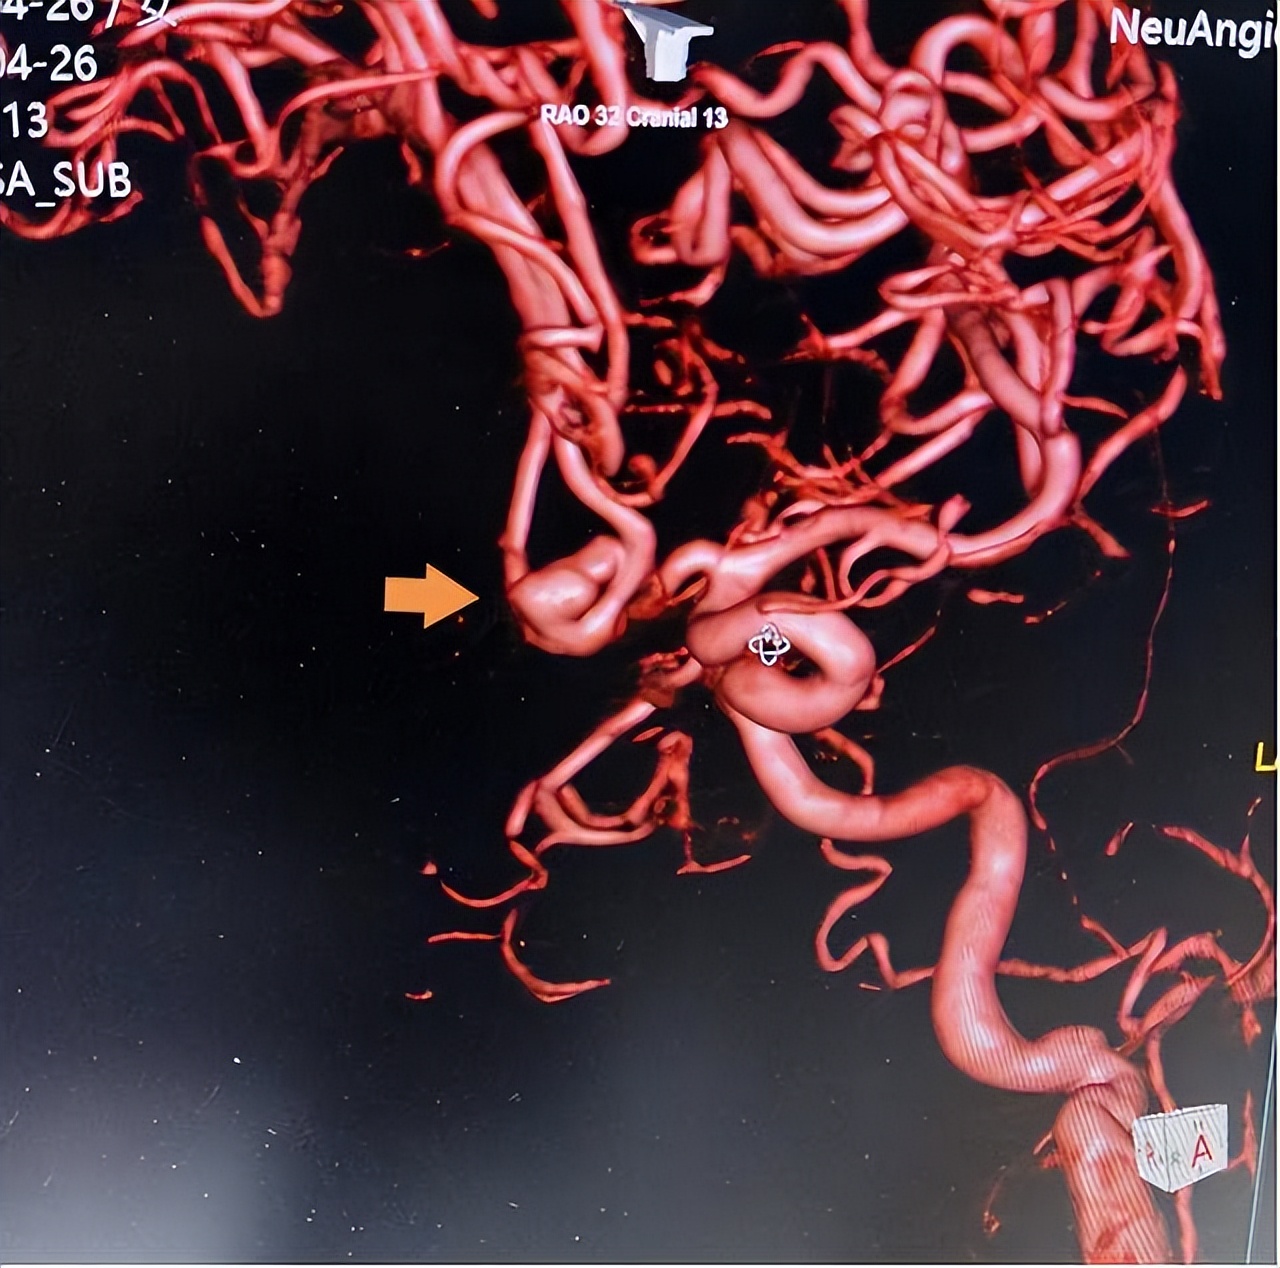

术前影像

时间就是生命!安居区人民医院卒中中心绿色通道立即启动,迅速安排头颈部CTA检查,很快锁定“罪魁祸首”——前交通动脉瘤!患者随即被收入ICU,但病情急转直下:呼吸困难、意识模糊……极有可能是动脉瘤再次破裂出血!若不立即手术,随时可能失去生命!与家属紧急沟通后,一场惊心动魄的“拆弹”手术即刻展开!

术中造影显示,刘女士的动脉瘤直径达8.5mm×7.0mm,形态复杂,尖端呈血泡样,这是动脉瘤中最凶险的类型之一,随时可能再次破裂!凭借精湛的技术和丰富的经验,专家团队沉着应对,成功实施“支架辅助弹簧圈动脉瘤栓塞术”,将这颗“炸弹”彻底“拆除”!